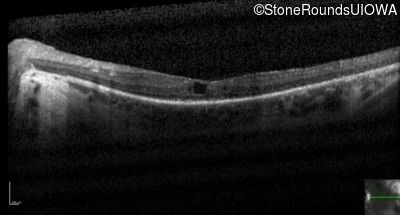

Optical Coherence Tomography - Left - 20/80 +2

Exemplar / OCT Stack